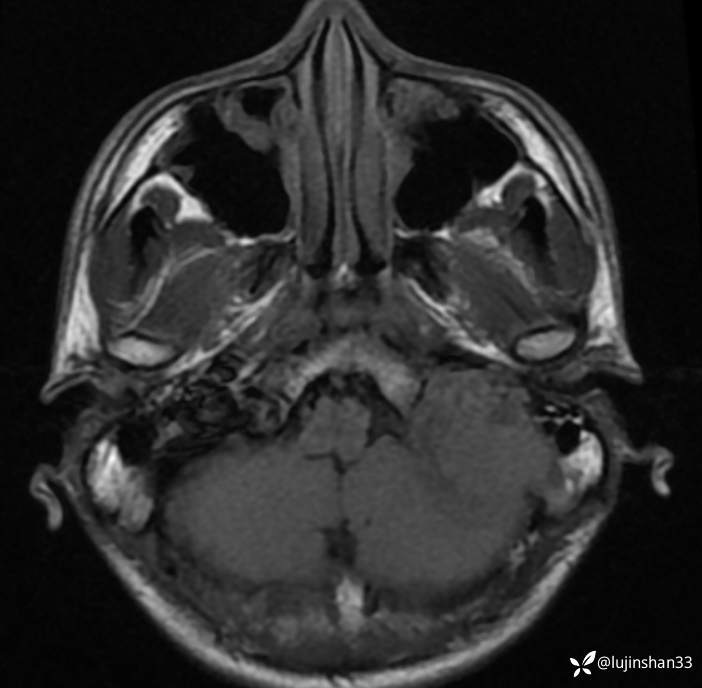

首次术前CT:

【现病史及既往史】:患者2年前无明显诱因出现左耳搏动性耳鸣、听力下降,耳鸣持续存在,伴轻度头晕,无眩晕及恶心、呕吐,无左侧外耳道流脓、流血,无视力下降,于2018-09-19在XXX市第一人民医院行颞骨CT及颅脑核磁示:左侧岩骨-桥小脑角区占位性病变,伴骨质破坏,考虑肿瘤性病变,于2019-02-19日于在我科住院行“经枕颈联合径路颞骨、颈静脉球窝及后颅窝肿瘤切除+腹部脂肪取出术腔填充+外耳道封闭”,病理结果(2019-2-19,我院)(左颞骨、左颞骨后颅窝、后颅窝硬脑膜) 富于破骨样巨细胞的肿瘤,背景为基质细胞梭形,界限不清,部分区域可见出血,局部见反应性骨形成,考虑为骨巨细胞瘤。送检瘤组织大小分别为1.2x1.2x0.7cm、7x6x2.5cm、3x2x0.8cm。(左颈部)淋巴结未见转移肿瘤(0/2)。免疫组化结果:p63(部分+),SATB2(+),Ki-67(+10%)。术后定期门诊随访,于2019-09-02行颞骨CT示:左侧颞骨骨巨细胞肿瘤术后改变,左后颅窝异常强化灶累及左侧颞骨斜坡,考虑复发,为进一步手术治疗来我院,以"颞骨骨巨细胞瘤术后(左)"收住入院。